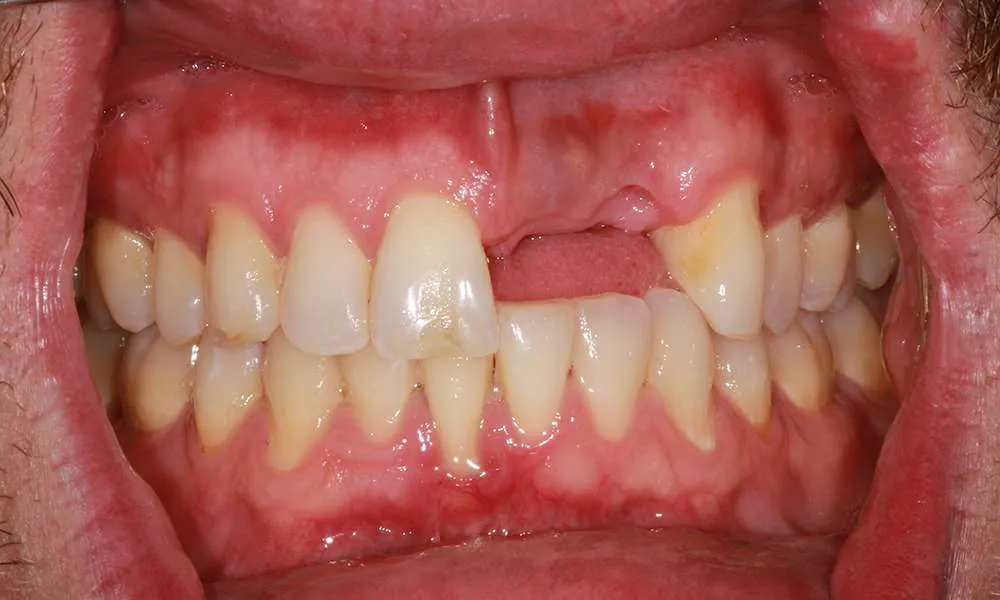

Real Stories, Real Results: Case Studies Showcasing How Our Personalized Approach Transforms Smiles and Lives

Complex Cases

Witness the Remarkable Changes We Can Achieve

While ultra-thin veneers are a fantastic option for many patients looking to enhance their smile, they may not be suitable for everyone. Ideal candidates are those with healthy teeth and gums who are looking to correct cosmetic issues like discoloration, misalignment/crooked or small gaps. During your consultation, Dr. O'Malley will assess your dental health and determine if ultra-thin veneers are the right choice for you.